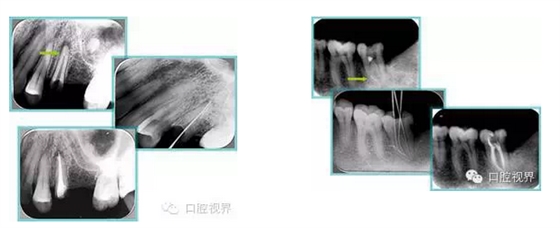

常見有修復性鈣化和增齡性鈣化。下面為根管鈣化 X 線片。

解決方法: ( 1 )清楚根管系統(tǒng)解剖形態(tài)。 ( 2 )安全頭的金剛砂鉆開髓,低速球鉆磨除鈣化牙本( ET20 ,ET40 ,DG-16 )。 ( 3 )徹底去除髓腔周壁的牙本質(zhì)齡。 ( 4 )借助化學性藥劑,如EDTA 等。

( 5 )初銼選用 8# 或 10#K 銼,平衡力法探察到工作長度 , H銼上下提拉法使根管擴大,提高工作效率

右圖及下圖為器械折斷的 X 線片。箭頭處示折斷器械。

解決方法: ( 1 )取出。 ( 2 )通過。 ( 3 )重新確定工作長度,充填。 ( 4 )根尖手術(shù)。

器械折斷可以不用取出,取出的原因多是患者心理因素。留在里面的器械關(guān)鍵是進行消毒,預(yù)防性使用抗感染藥物,預(yù)防感染。